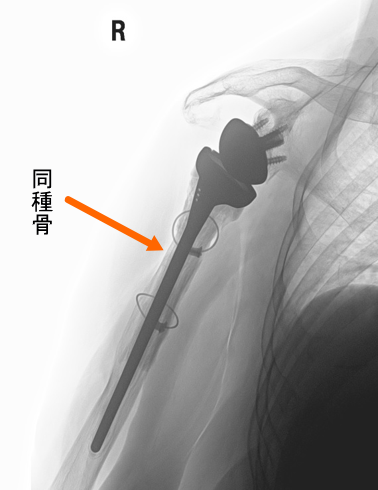

手術3年

術後3年

同種骨は3年たっても上腕骨に固定され、ステムは上腕骨にしっかり固定されています